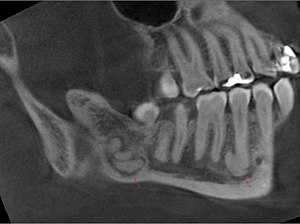

Ameloblastoma is the most common odontogenic tumor. It is usually benign but often recurs. It is a cystic poorly circumscribed mass. It grows destructively.

- on X-ray it looks like a circumscribed clearing